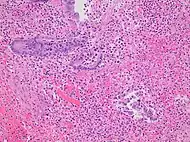

Pathology diagnosis of appendicitis can be made by detecting a neutrophilic infiltrate of the muscularis propria.

Classification of acute appendicitis based on gross pathology and light microscopy characteristics[72]

PatternGross pathologyLight microscopyImageClinical significance

Acute intraluminal inflammation None visible

• Only neutrophils in lumen

• No ulceration or transmural inflammation

Probably none

Acuta mucosal inflammation None visible

• Neutrophils within mucosa, and possibly in submucosa

• Mucosal ulceration

May be secondary to enteritis.

Suppurative acute appendicitis May be inapparent.

• Dull mucosa

• Congested surface vessels

• Fibropurulent serosal exudate in late cases

• Dilated appendix

• Neutrophils in mucosa, submucosa and muscularis propria, potentially transmural.

• Extensive inflammation

• Commonly intramural abscesses

• Possibly vascular thrombosis

Can be presumed to be primary cause of symptoms

Gangrenous/necrotizing appendicitis

• Friable wall

• Purple, green or black color

• Transmural inflammation, obliterating normal histological structures

• Necrotic areas

• Extensive mucosal ulceration

Will perforate if untreated